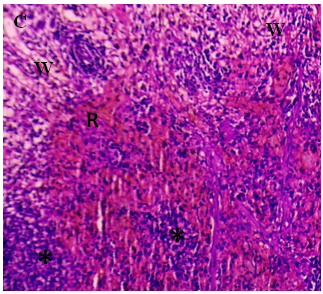

The current investigation focused on spleen histopathology to examine the overall condition of the organ. Elmore (2006), R. E. Mebius and G. Kraal (2005), as well as other sources, were used to anatomize the histopathological differences shown in fig. 114,15. Fig. 1 shows normal histoarchitecture in the control spleen tissue of a male albino rat, with sufficient amounts of red pulp (R), white pulp (W), lymphoid follicles (LF), and marginal zone (MZ). Table 2 has detailed histology observations. The histological structures in the cyphenothrin-treated group were well terminated, just like in the control group. The red pulp in the group that received high doses of the pesticide cyphenothrin showed decreased cellularity, while the white pulp was severely destroyed, with no normal lymphoid follicle and boundary zone. White pulp and red pulp from the low-cure cyphenothrin group showed destroyed cellular integrity. This cyphenothrin-treated group, which included high and low doses, demonstrated notable modifications of histological structures in contrast. In comparison to the cyphenothrin high dosage group, the white pulp recovered effectively in the cyphenothrin insecticide low dose treatment group.

Fig. 1: (A) and (B) Spleen sections of control rats: (R) red pulp; (W) white pulp; (LF) lymphoid follicle; (MZ) marginal zone; (PALS) Periarteriolar lymphoid sheath. H and E, x100. (C) and (D) Spleen structure of rat treated with cyphenothrin (63.6 mg/Kg BW) respectively: arrow head Show a thin damaged marginal zone (MZ), asterisk (*) indicates decreased cellularity (rarefication) and altered structural integrity of white pulp, H and E, 100×. (E) and (F) spleen tissues of cyphenothrin treated (35.33 mg/Kg BW) respectively: arrow shows damaged tissue region, marginal zone (MZ) and lymphoid follicles (LF). H and E, 100